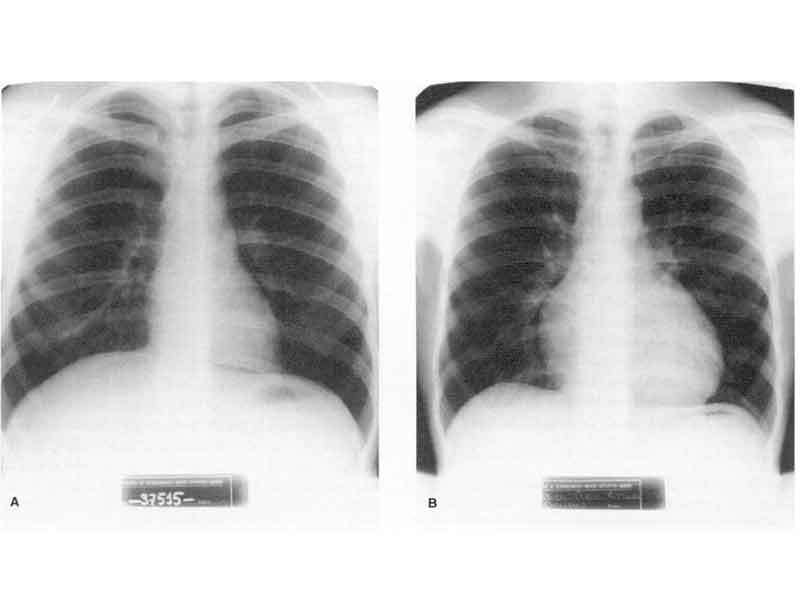

En la imagen superior puedes ver radiografías comparadas del tórax, en las que se aprecia la diferencia de tamaño entre las siluetas cardiacas de un sujeto sedentario (izquierda) y un corredor de maratón (derecha). Tomado de López Chicharro J. y Fernández Vaquero A. "Fisiología del ejercicio". 3ª ed. Panamericana, 2006.

Radiografías comparadas del tórax con las siluetas cardiacas de un sujeto sedentario (izquierda) y un corredor de maratón (derecha)